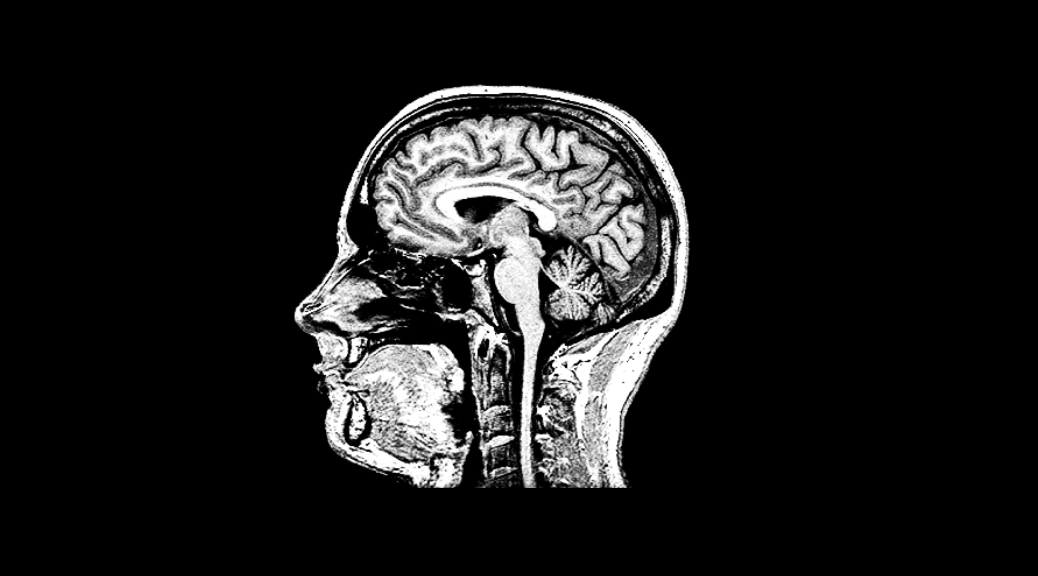

If you get an MRI scan done, they provide you a CD with the images. However, these images are in a binary format and can only be viewed using the Windows based software on the CD. What do you do if you have a Mac or a Linux PC? OR if you want to share the images online? Here is a Python script that can help.